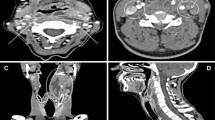

In five cases (3.5%) we found pneumonic infiltrates, which were visible only above diaphragmatic dome (Fig. 4 and 5). There were no other findings above the diaphragmatic dome, which could be reported as an infectious focus, so the diagnostic efficacy of thoracic imaging with regard to an infectious focus was 3.5% (95%-CI: 0.5–6.5%).

In one of these five cases, antibiotic therapy was initiated due to the imaging diagnosis of pneumonic infiltrate. In the other four cases, there was no change in patient management due to the reported pulmonary infiltrate on CT, so the therapeutic efficacy of thoracic imaging with regard to an infectious focus was 0.7% (95%-CI: 0–2.1%).

There were some other pathologic findings only visible above the diaphragmatic dome (Fig. 4). In one case (0.7%) we could not exclude peripheral pulmonary artery embolism, but this did not influence patient management. In seven cases (4.9%) we found catheter-associated thromboses (Fig. 5), which in no case led to changes in patients’ management, since all patients already received anticoagulation. In three cases (2.1%) we found endotracheal tube malposition in the right main bronchus (Fig. 5) and in one case (0.7%) we found chest tube malposition within the soft tissues of the chest wall. These findings were already visible and reported on previous chest X-ray imaging. In one case (0.7%), there was a pulmonary nodule above the diaphragmatic dome. This was a known metastasis of colorectal cancer, which was equal in size (6 mm) compared to the last staging CT six weeks prior. In eight cases (5.6%) pulmonary congestion was found only above the diaphragmatic dome. Pulmonary congestion was very mild in all cases, in five of these cases it was already known prior to CT and treatment had already been initiated. In the remaining three cases fluid overload was not considered clinically relevant (in accordance with the mild extent on CT), and therefore, no change to patient management was made. Overall, therapeutic efficacy of thoracic imaging exceeding the primary goal of identifying an infectious focus was 0%.

Examples of imaging findings on thoracic CT above the diaphragmatic dome. Left: Coronal contrast enhanced CT showing pneumonic infiltrate in the right upper lobe. Middle: Coronal contrast enhanced CT showing endotracheal tube malposition in the right main bronchus. Right: Coronal contrast enhanced CT showing catheter-associated thrombosis in the left brachiocephalic vein